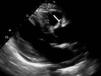

Mulher de 67 anos, com antecedentes de esclerodermia e hipertensão arterial, sem sintomas cardíacos prévios, foi internada para avaliação do envolvimento sistémico da esclerodermia. Ao exame objetivo apresentava um sopro sistólico no apex grau ii/vi. O eletrocardiograma revelou ritmo sinusal e bloqueio fascicular anterior esquerdo. O ecocardiograma mostrou na incidência para-esternal esquerda eixo longo uma imagem tubular anómala em continuidade com a parede anterior da aorta ascendente (Figura 1). Em para-esternal eixo curto a nível da aorta é visível a mesma estrutura tubular circundando a aorta (Figura 2). Em apical quatro câmaras observou-se a imagem tubular com 2mm de diâmetro com 42mm de comprimento, transversal ao septo interauricular. Não foram identificados a origem e o fim da estrutura. Com Doppler de cor observou-se fluxo no seu interior (Figuras 3 e 4). Pelo facto de se suspeitar de uma estrutura vascular, realizou-se cateterismo cardíaco, que revelou uma origem anómala da artéria coronária esquerda (ACE) a partir do segmento proximal da coronária direita com trajeto epicárdico e anterior à aorta (Figura 5). Os achados ecocardiográficos mais associados à esclerodermia são a hipertensão pulmonar e o envolvimento pericárdico incluindo a pericardite fibrinosa. Não há casos descritos da associação entre esclerodermia e origem anómala das artérias coronárias, pelo que este caso poder-se-á tratar de uma coincidência. A origem da ACE a partir do óstio da coronária direita ocorre em apenas 0,15%1 da população, estando associada a morte súbita2.